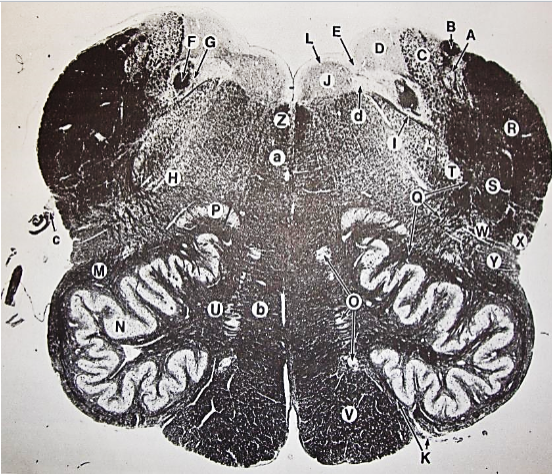

A

Fasciculus gracilis

B

gracile nucleus

C

fasciculus cuneatus

D

cuneate nucleus

E

spinal trigeminal tract

F+G collectively

spinal trigeminal nucleus

H

accessory nucleus

I

pyramidal decussation

J

rubrospinal tract

K

posterior spinocerebellar tract

L

anterior spinocerebellar tract

M

lateral spinothalamic tract

N

anterior spinothalamic tract

O

lateral vestibulospinal tract

P

medial longitudinal fasciculus

Q

tectospinal tract